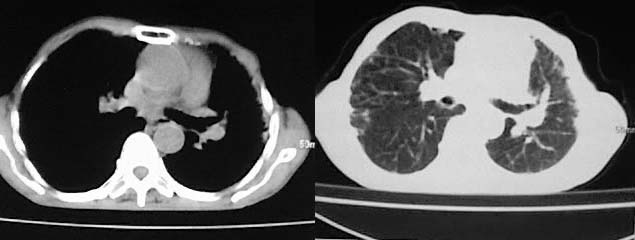

以下是引用有风的日子在2008-5-2 12:13:00的发言:[br][emb10][br][br]肺ca?有病理支持吗?[br][br]我看更象是肺tb并支扩、间质性肺炎。最好拿个病理结果来,不然这点影像资料诊断肺ca是难以服人的![br][br]至于主动脉瘤的诊断问题,国外认为≥4.0cm就可诊断了,国内对此诊断标准更为严格。患者升主动脉明显增粗,即>4cm。你诊断个升主动脉扩张并不为过!

以下是引用zjzjr在2008-5-2 14:39:00的发言:[br]支持双侧继发型肺结核,左侧胸膜肥厚,慢性支气管炎伴间质纤维化.